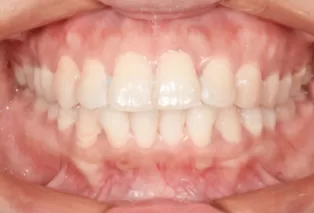

Photos intra-orales